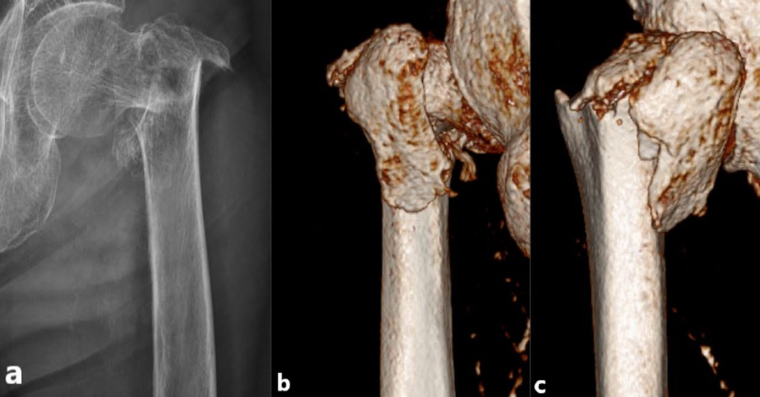

近年来,来自北医三院周方教授团队提出的PFUN,即proximal femoral universal nail system,股骨近端通用髓内钉系统,旨在通过增加内外侧壁的额外固定,即增加小转子螺钉,大转子冠状面螺钉或外侧钢板等,同时重建内外侧壁稳定性:

▲ 图A所示为PFUN系统中,小转子螺钉(c)与外侧壁螺钉(b),图B所示冠状面螺钉(c)。

▲ 图C所示为小转子螺钉(c)与外侧壁钢板(d);图D所示为PFUN三维力图模型。